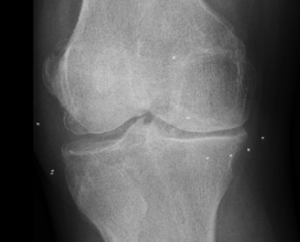

Los implantes de oro periarticulares actúan en las partes blandas de la articulación y es claro el beneficio clínico que se obtiene. Pero hasta ahora no se había objetivado el rol de los implantes a nivel del cartílago hialino en pacientes humanos. A continuación se observan las RX de un paciente octogenario con gonartrosis bilateral y genu varo tras dieciocho (18) meses de colocación de implantes. La buena evolución clínica es paralela a los cambios radiológicos que se observan especialmente en la articulación tibiofemoral interna en donde la degradación cartilaginosa es mayor. Se comparan las radiografías anteriores y posteriores a los implantes, con un aumento significativo de la interlínea articular.